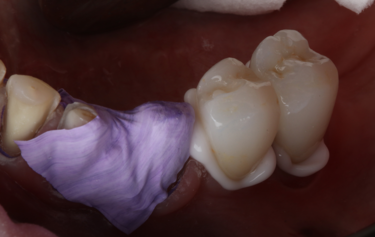

Figure 7: Indirect orthodontic bracket bond-up stents in-situ

Figure 8: Immediate result after stent-guided composite build-up and orthodontic bracket placement

The full restoration of all the patient’s upper and lower teeth was completed using this process at the same visit in only 2 hours. We were able to immediately then place upper and lower orthodontic brackets using an in-direct set-up technique through CFast orthodontics. This stent-guided application method means a much quicker and simpler fixation of the bracket to the teeth. Due to the incredible accuracy of the SmileFast stent, the composite restorations placed are a perfect replication of the digital model on which the orthodontic set-up was manufactured, therefore the stent for the orthodontics was a perfect fit, as shown in Figure 7. Within 4 hours all the patient’s teeth were fully restored and the fixed orthodontics applied and activated with 0.014 NiTi wires (Fig. 8). After 5-months the teeth were aligned into a more favourable position and the passive over-eruption of the teeth had been reversed (Fig.9). The patient was comfortable and occlusion functioning well, so it was decided to move forward with the second phase of her rehabilitation, the planning and provision of her final ceramics.